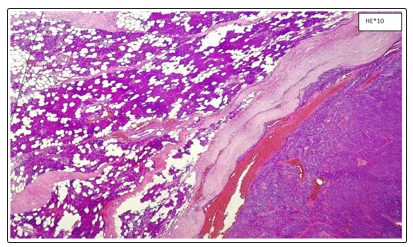

- Microscopic examination showed a benign tumor proliferation encapsulated compact architecture, in situ clusters and channels with eosinophilic content. The epithelial cells have a basaloid appearance bordered at the periphery by a palisade cell base. They are of small to medium size, provided with ovoid cores with fine chromatin. The cytoplasm is abundant basophilic. The myoepithelial cells are sometimes cuboid, sometimes fusiform. The nuclei are discreetly elongated hyperchromic. The cytoplasm is scarce eosinophilic (Figures 2, 3, 4). The massive elm form (3 cases) and the menbranous form (1 case)

Figure 2: Parotid Salivary Parenchyma With Well-Limited Tumor Proliferation Encapsulated